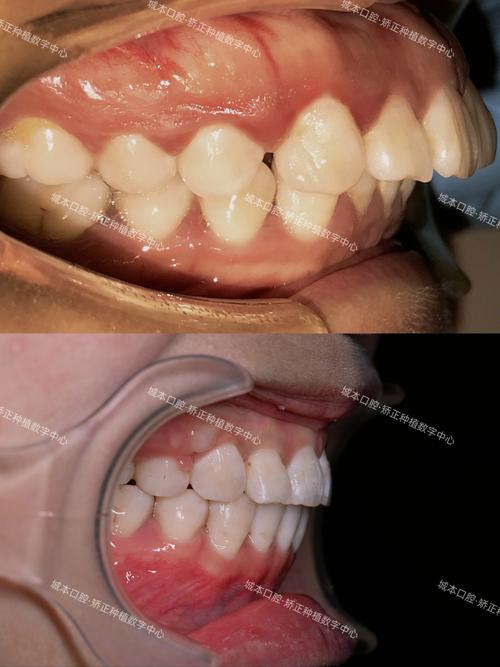

牙齿正畸中“深覆盖”和“露牙龈”是两个常见但性质不同的口腔问题,它们经常同时出现,但原因和治疗方法需要分别考虑,下面我为你详细分析一下:

🦷 1. 深覆盖 (Deep Overjet / Class II Malocclusion)

- 定义: 指的是上颌前牙(尤其是上颌中切牙)相对于下颌前牙过度向前突出,简单说就是“龅牙”,上下牙在咬合时,上牙切缘到下牙切缘的水平距离过大(正常通常在2-4mm以内)。

😬 2. 露牙龈 (Gummy Smile / Excessive Gingival Display)

- 定义: 指在微笑时,上颌前牙区牙龈暴露过多,超出正常范围(通常认为微笑时上中切牙暴露2-4mm牙龈是正常的,超过这个范围就是露牙龈)。

- 经常并存: 上颌前突(深覆盖的主要原因之一)常常伴随着上颌垂直向发育过度(露牙龈的主要原因之一),很多患者同时存在这两个问题。

- 相互影响: 上颌前突会使上牙更靠前,更容易在微笑时暴露牙龈;而上颌垂直向发育过度本身就会导致露牙龈,同时也会加重深覆盖的视觉效果。